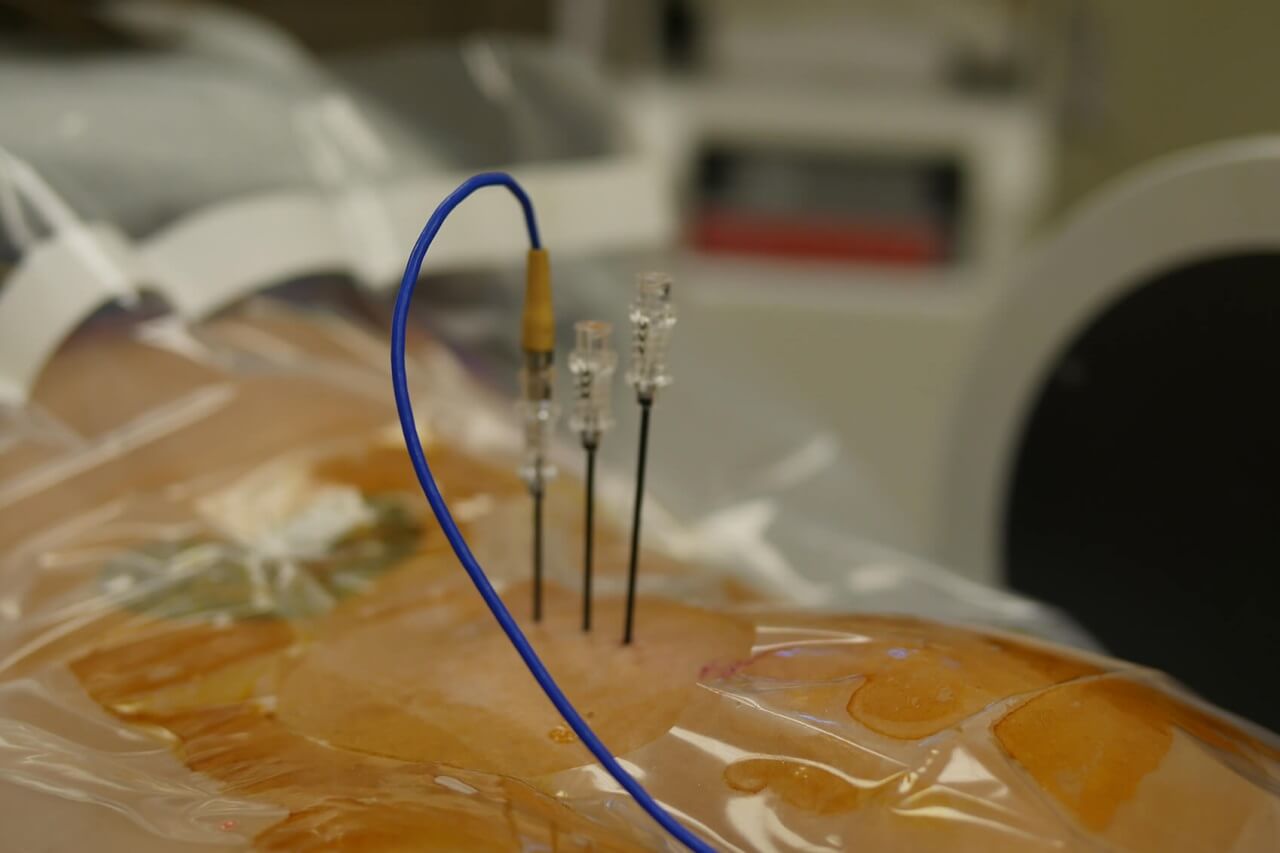

Несмотря на высокую информативность визуализационных методов исследования, применяемых в клинике Ассута, для установления точного диагноза в ряде случаев требуется более детальное изучение патологически измененных тканей. Особенно актуальным это становится при подозрении на онкозаболевания. С помощью проведения биопсии израильским специалистам удается безошибочно устанавливать не только характер новообразования, но и его гистологический тип и другие опухолевые характеристики.

Врачи клиники Ассута используют самые передовые и щадящие методы забора тканей для последующей цитологической и гистологической диагностики с помощью ультрасовременных микроскопов высокого разрешения. При этом для пациентов данное исследование является не только абсолютно безопасным, но и доступным. Стоимость биопсии в Израиле намного ниже, чем в других странах с аналогично развитой медициной, а точность ее результатов всегда стопроцентна.